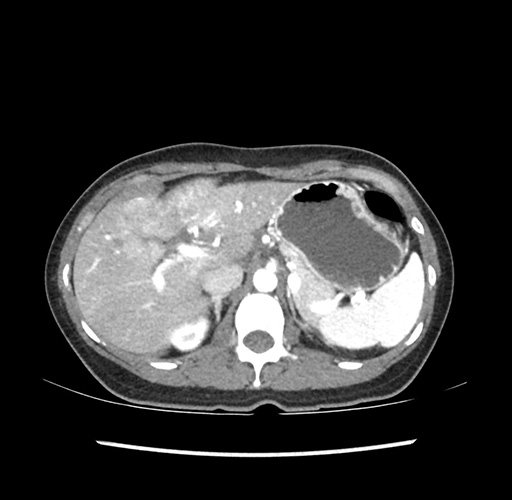

Left lateral sectionectomy [case 12]

Imaging Analysis

Look through the patient's CT scan to identify any areas of concern for the necessary procedure.

Based on your CT findings, which issue(s) would give reason for "planned slowing down moment(s)" in this case?

Considering a standard left lateral sectionectomy procedure, what step(s) of the operation would you do differently in this case ?